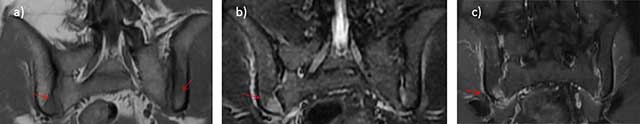

Figure 4

Stress fractures of the sacrum postpartum. Transversal T1 a), STIR b), and coronal T2 c) Images show two thin fractures lines, of low T1 and high T2 signal, located at 1–2 cm of the sacroiliac joints (arrows) and associated with bone marrow edema.